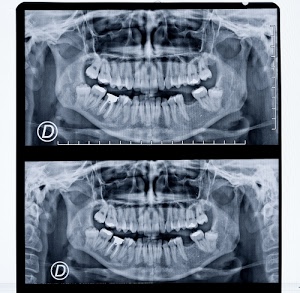

29° I raggi X o raggi Röntgen Autore: Diana Cocco - Voto: 0 |  30° Bocca della Verità Autore: giuseppedip - Voto: 0 |